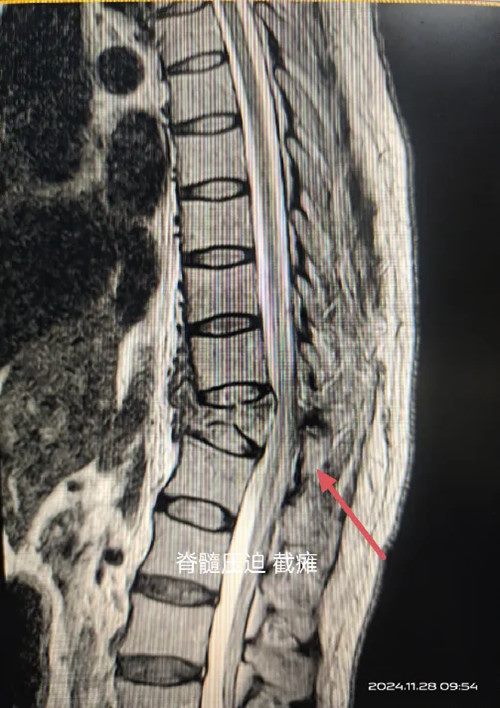

诊断为胸椎爆裂骨折并截瘫

FrankelB级属严重脊髓损伤

核磁显示骨折块压迫,局部脊髓变细

如不尽快解除压迫将造成不可逆性损伤

瘫痪等严重后果